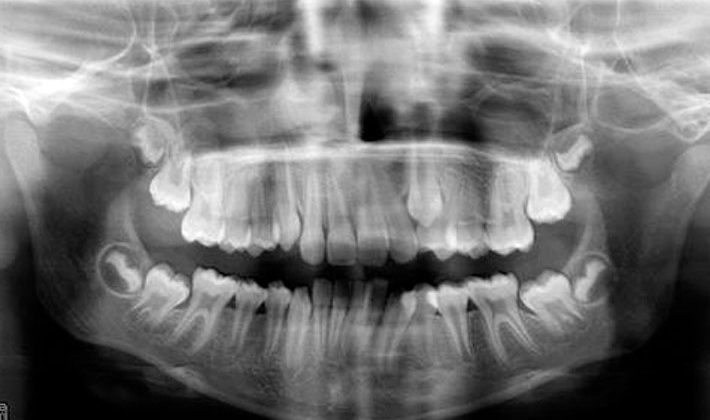

Las imágenes radiográficas son una información básica a la hora de tomar decisiones terapéuticas.

Ni siquiera las bajas dosis de radiación están exentas de riesgos. Un porcentaje importante de las exploraciones dentales se realizan a niños y a jóvenes, cuyos órganos son 10 veces más sensibles que en los adultos. Por ellos estamos obligados a utilizar estas técnicas diagnósticas con cautela y siempre en relación a los beneficios que éstos nos aportan.